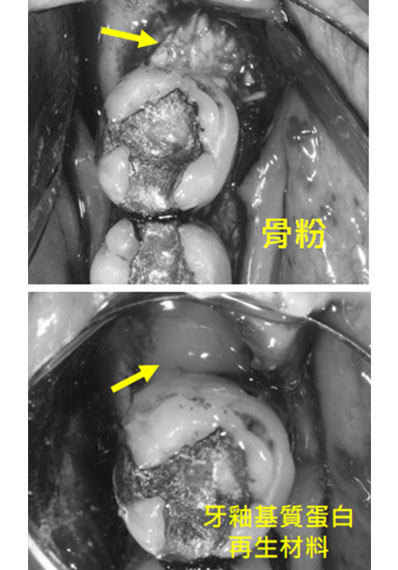

手術中

將骨頭缺失的地方,放骨粉及牙釉基質蛋白再生材料,將其縫合.........後續追蹤